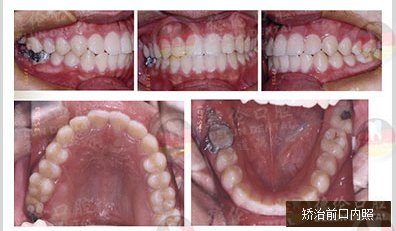

男 17岁

牙齿症状:下颌右侧第二、第三磨牙水平阻生,下颌左侧第三磨牙水平阻生

矫治方法:下颌拔除两颗第三磨牙(智慧齿)

发表于全球口腔正畸学界著名杂志J.Clin.Orthod